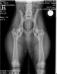

Elli Mae hips : Ellie Mae Vom Sucherquelle

Elli Mae